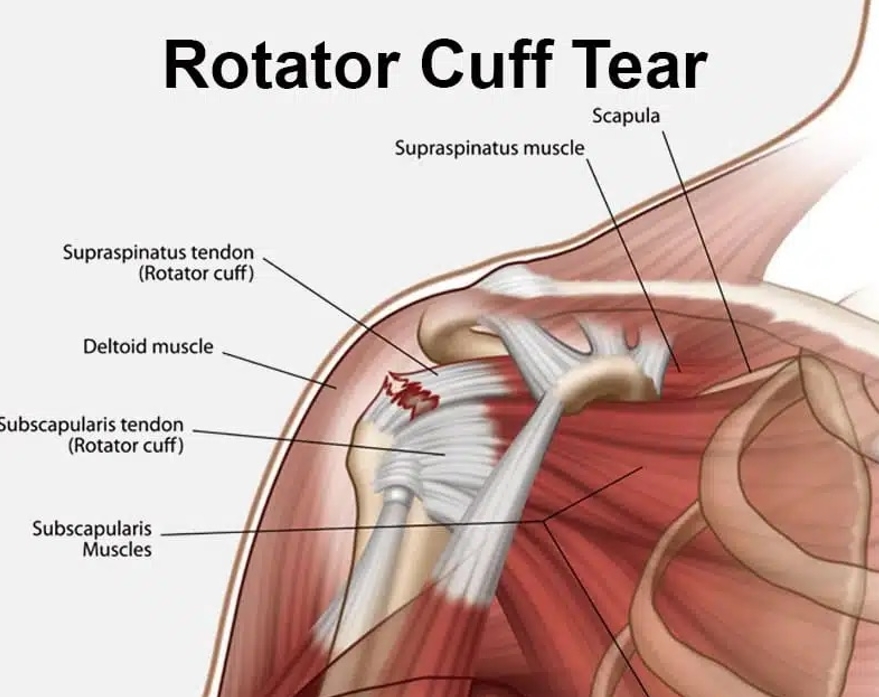

什麼是肩袖肌群?

肩袖肌群 (Rotator Cuff Muscles Group) 是一組由四塊肩膀肌肉及肌腱組成的結構,負責穩定肩關節並使肩膀具備多樣化的活動能力。這些肌肉對於抬高及旋轉手臂至關重要,同時肩袖還有助於將上臂骨 (肱骨,Humerus) 的球狀部分牢固地保持在肩胛骨 (Scapula) 的關節窩內。

當肩袖受傷時,可能會導致肩膀疼痛、活動受限,甚至無法正常使用手臂。